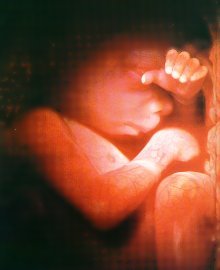

0 - 16 Week Development

Six weeks after conception, the baby is an identifiable human form.  The heart has been beating for three weeks and brain waves are detectable.  You can see the blood being pumped into the baby's heart.  The blood is flowing from the placenta through the umbilical cord into the liver.  The baby's ear, eyes, and the tiny hands and feet are clearly noticeable.